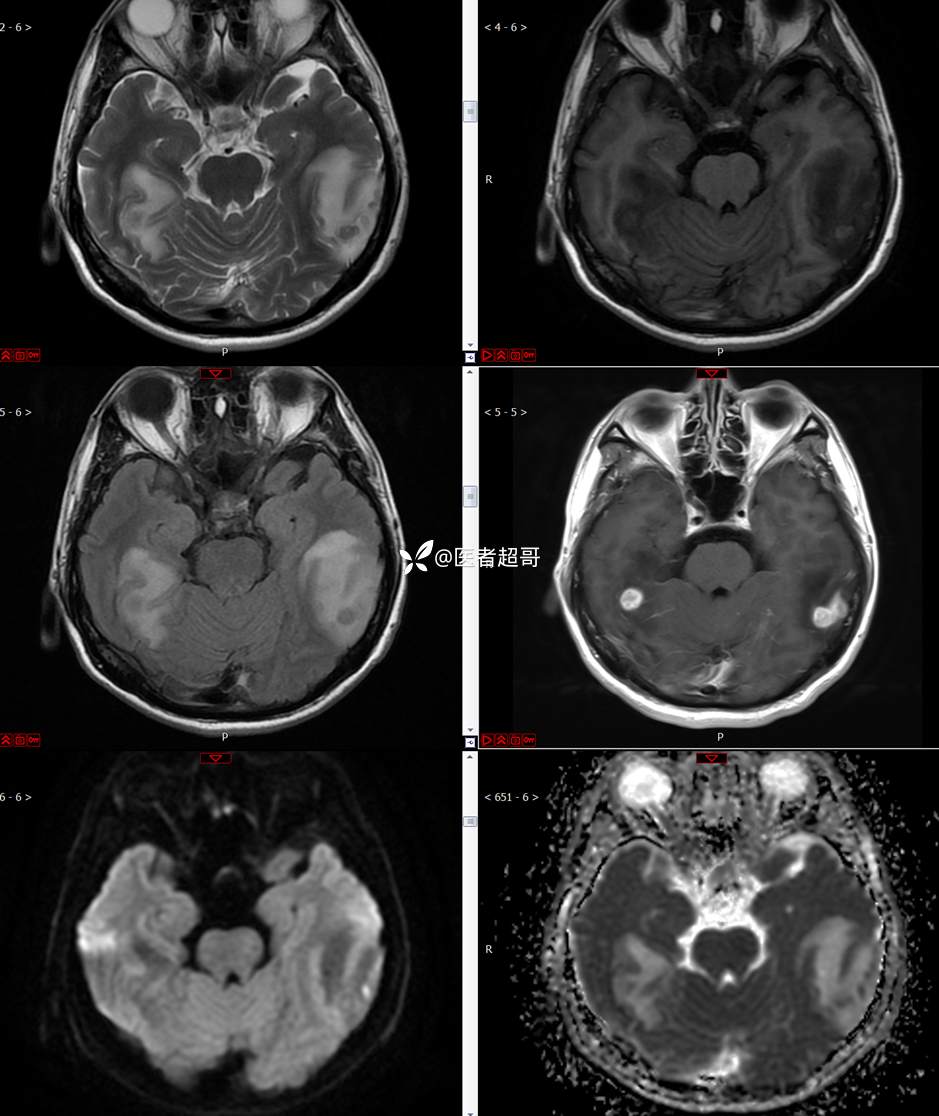

【影诊笔记773】头痛、头晕10天,CT、MRI齐全,请高诊!

主 诉:头痛、头晕10天

现病史:患者10天前无明显诱因感头痛、头晕,伴记忆力减退,无恶心、呕吐,无肢体抽搐及肢体活动不灵等,于我院就诊,行颅脑MR示颅内多发占位,现患者为求进一步治疗于我院就诊,以“颅内占位”收入我科。患者目前神志清,精神可,饮食、睡眠正常,体重无明显变化。

既往史:既往急性肝功能衰竭病史.